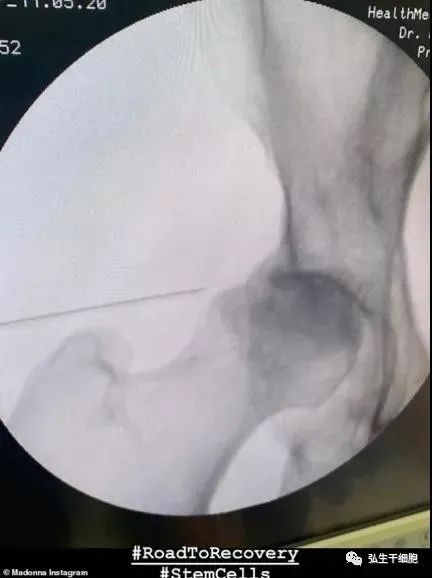

此前,泰森与篮球传奇人物大鲨鱼沙奎尔·奥尼尔视频聊天时就曾透露,他计划今年晚些时候会复出。通话中,泰森透露自己接受了干细胞治疗,且经过干细胞治疗后效果非常棒,感觉自己变成了另外一个人。

不过泰森一直没有透露过自己是为什么要接受干细胞治疗的手术,大家对于泰森患了什么疾病一无所知。有很多粉丝们猜测,泰森很有可能和拳王阿里一样,患上了帕金森或阿尔兹海默症。在接受手术之后,泰森表示感觉自己又充满了年轻的活力,他认为自己的身体“焕然一新”了。